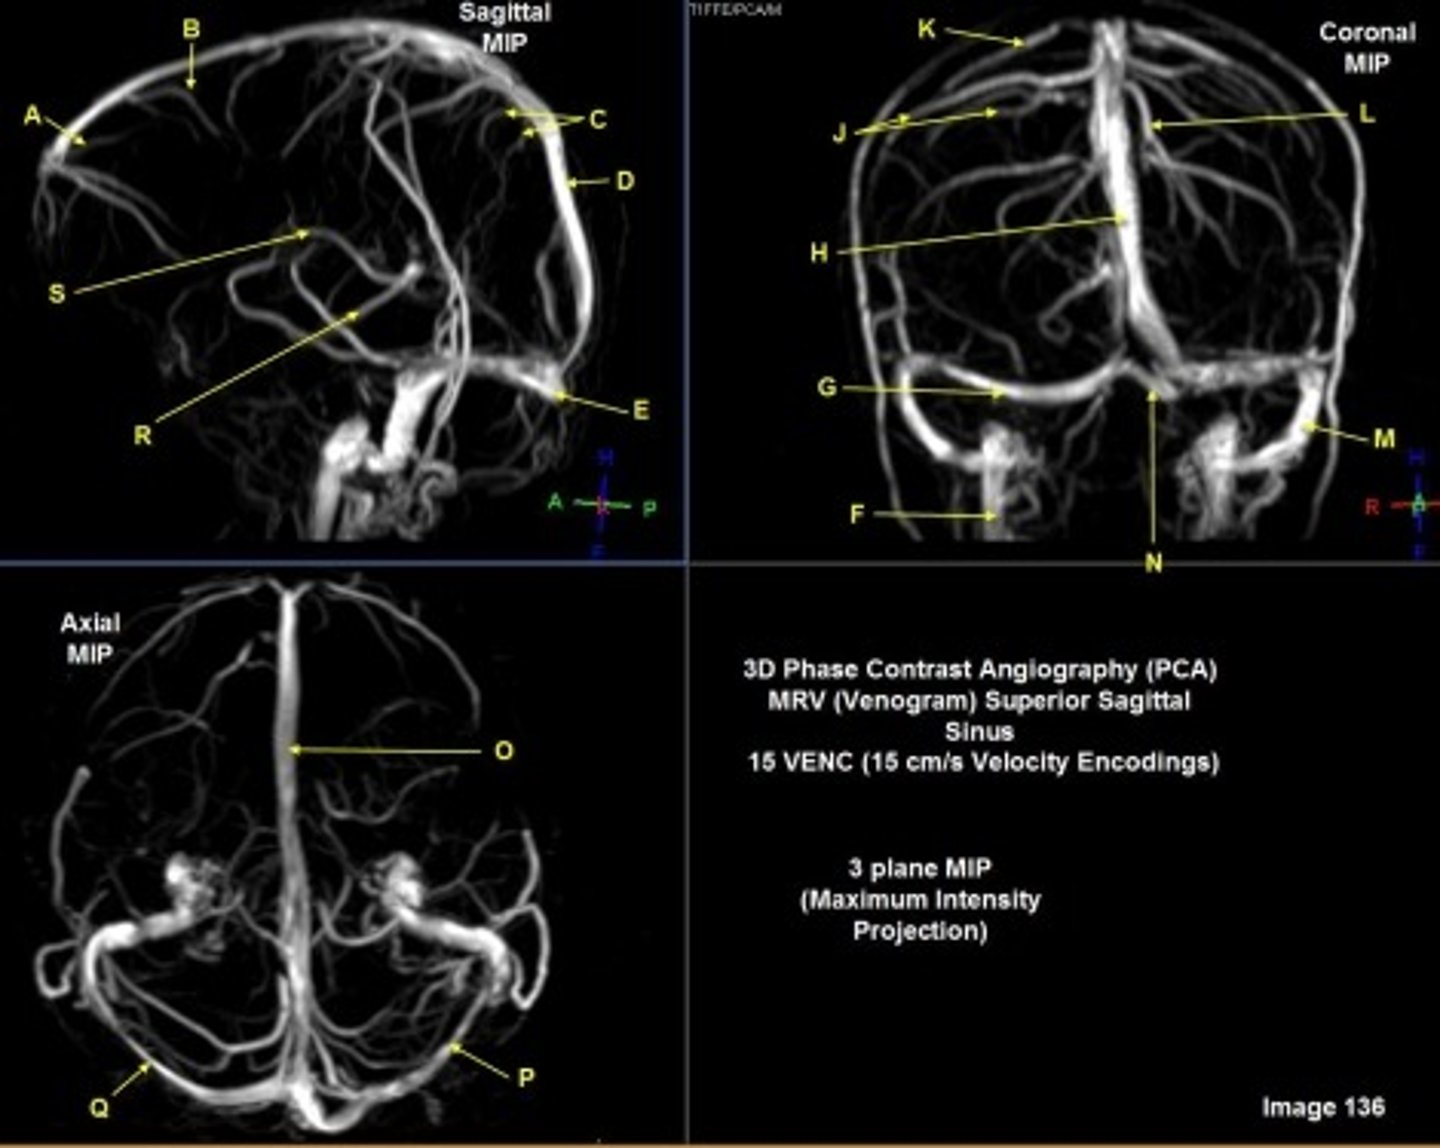

A

Internal carotid artery

B

Caudate nucleus

C

white matter

D

thalamus

F

straight sinus

G

lateral ventricle

H

lateral sulcus

L

optic chiasm

O

Splenium of corpus callosum

V

Cerebral peduncle

W

superior sagittal sinus

X

vein of galen

Y

Inferior colliculus of midbrain,

just inferior to pineal gland / superior to the cerebral aqueduct

Letter N in Image 137 is pointing to what type of tissue?

The corpus callosum is the only white matter tissue structure found in the midline sagittal slice of the brain.